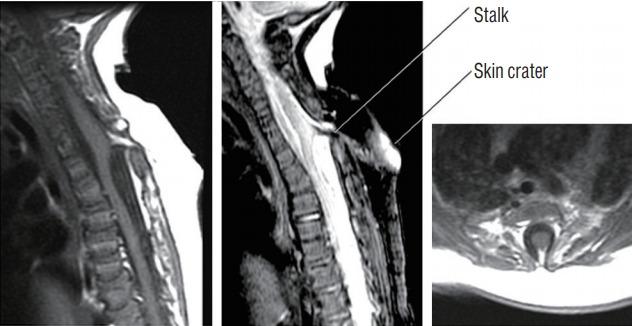

Spinal dysraphic lesions due to focal nondisjunction in primary neurulation are commonly encountered in paediatric neurosurgery, but the "fog-of-war" on these conditions was only gradually dispersed in the past 10 years by the works of the groups led by the senior author and Prof. Kyu-Chang Wang. It is now clear that limited dorsal myeloschisis and congenital spinal dermal sinus tract are conditions at the two ends of a spectrum; and mixed lesions of them with various configurations exist. This review article summarizes the current understanding of these conditions' embryogenetic mechanisms, pathological anatomy and clinical manifestations, and their management strategy and surgical techniques.

由于原发性神经管形成过程中的局灶性不分离导致的脊柱裂病变在小儿神经外科中很常见,但在过去10年中,由资深作者和王宇辰教授领导的团队的工作才逐渐驱散了这些病症上的“战争迷雾”。现在已经明确,有限性背侧脊髓裂和先天性脊柱皮样窦道是同一谱系两端的病症;并且存在各种形态的它们的混合病变。这篇综述文章总结了目前对这些病症的胚胎发生机制、病理解剖和临床表现,以及它们的治疗策略和手术技术的认识。